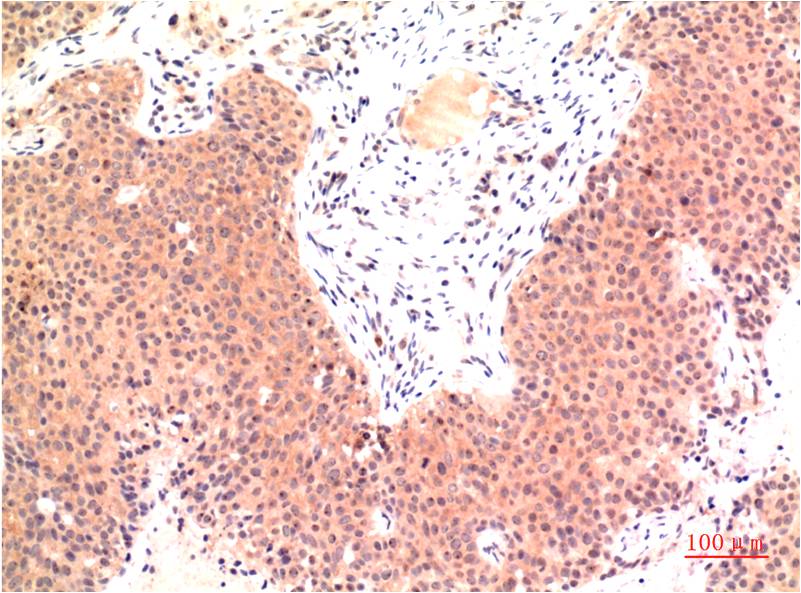

• Immunohistochemical analysis of paraffin-embedded Human tonsils using epsilon Tubulin (4C4) antibody.High-pressure and temperature Sodium Citrate pH 6.0 was used for antigen retrieval.